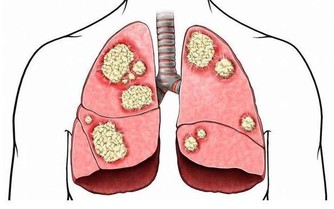

而尿騷味,則通常提示腎有問題了。

人體腎臟具有強大的代償功能,只要腎功能喪失不超過75%,仍能保持人體內環境的穩定。

所以,慢性腎衰病人早期常無明顯臨床症狀,往往容易誤診、漏診,使腎衰病人失去最佳的治療時機。

另外,一些慢性腎衰病人還有一些特殊的臨床表現,如口腔內有氨的氣味,也就是你說的尿味,尿毒症病人更為明顯。

主要原因是,隨著腎功能的減退,腎臟的溶質清除率下降和某些肽類激素的滅活減少,造成多種毒素在血液和組織中蓄積,最常見的毒素就是尿素等。

在口腔中,因為唾液中的尿素被分解為氨,故病人呼出的氣體有尿味。

這種氣味的濃淡隨病情的進退而變化,在病情好轉時,口中尿味淡些,病情加重時尿味變濃。